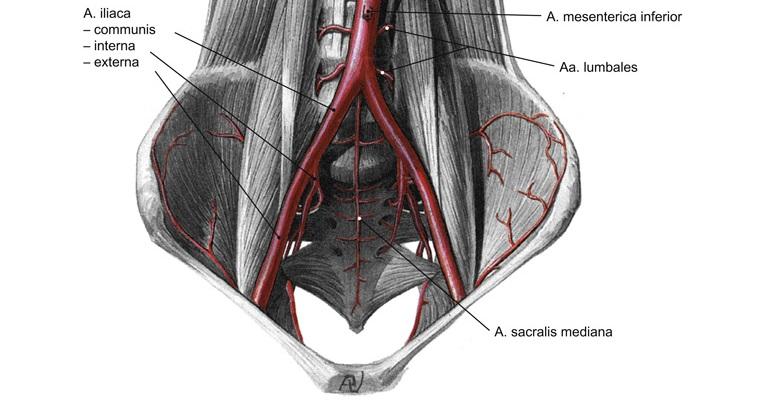

Fig 3.26: a. iliaca communis

|

Fig 3.27: a. iliaca interna - dorsale hoofdstam

A doorsnede

os pubis sacrum -

a iliolumbalis

a sacralis lateralis -

a glutea superior

r superficialis r profundus

B vooraanzicht

C zijaanzicht

os coxae > os ilium lig sacrotuberale -

lig sacrospinale